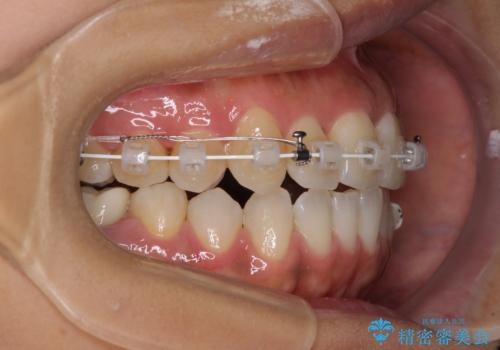

【モニター】幅の狭い上顎歯列 骨幅を拡大する矯正治療

上顎骨の横幅が狭く、歯列が混み合っていたため、急速拡大装置により側方拡大し、咬み合わせと歯列を改善することとしました。

骨格的な問題を解決したことで、下顎は部分矯正で対応することができました。